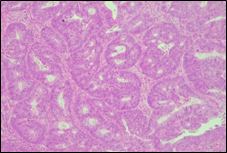

The present study concluded that, out of the total 77 patients with colorectal neoplasia, 17 (22.1%) had a high degree of differentiation (G1), 51 (66.2%) had a moderate degree of differentiation (G2), and 9 (11.7%) had a low degree of differentiation (G3). Figure 3 illustrates the different morphopathological forms of colorectal neoplasia observed in the patients included in the study.

A | B |

C | |

Fig. 3 Morphopathological forms of colorectal tumors (degree of differentiation) A – conventional highly differentiated colonic adenocarcinoma (G1) (HE stain, ×200) B – moderately differentiated (G2) conventional colonic adenocarcinoma (HE stain, ×200) C – conventional poorly differentiated colonic adenocarcinoma (G3) (HE stain, ×200) | |

For patients with colorectal neoplasm, investigating the correlation between the macroscopic aspect of the tumor formation visualized endoscopically and the degree of differentiation described histologically, it was found that there is no statistically significant relationship (p > 0.05), which is above the threshold accepted for demonstrating a significant statistical correlation. It is known that most colorectal adenocarcinomas develop at the site of precursor lesions, such as adenomas and dysplasia. Residual adenoma is a phenomenon commonly found in colorectal adenocarcinomas. Typical adenomas are subclassified into tubular, tubulovillous, and villous types based on their architectural and histological features. Tubular adenomas consist of dysplastic glands that resemble cryptic intestinal glands and contain less than 25% villous component. Villous adenomas are composed of more than 75% villous components, which appear as fibrovascular rods covered by dysplastic epithelium. Tubulovillous adenomas represent intermediate lesions with a villous component ranging from 25% to 75%.